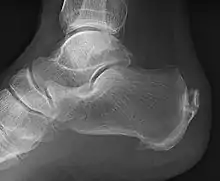

| A radiograph showing osteophytes on the posterior and inferior aspects of the calcaneus | |

A calcaneal spur (also known as a heel spur) is a bony outgrowth from the calcaneal tuberosity (heel bone).[1] Calcaneal spurs are typically detected by x-ray examination.[2] It is a form of exostosis.

An inferior calcaneal spur is located on the inferior aspect of the calcaneus and is typically a response to plantar fasciitis over a period, but may also be associated with ankylosing spondylitis (typically in children). A posterior calcaneal spur develops on the back of the heel at the insertion of the Achilles tendon.[3]

An inferior calcaneal spur consists of a calcification of the calcaneus, which lies superior to the plantar fascia at the insertion of the plantar fascia. A posterior calcaneal spur is often large and palpable through the skin and may need to be removed as part of the treatment of insertional Achilles tendonitis.[3]